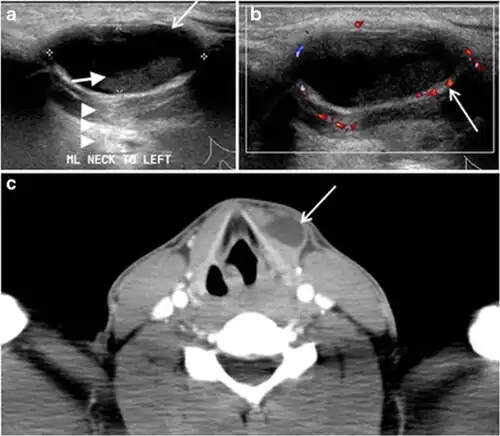

Fig. 9. A 58-year-old male patient with persistence PTC at thyroid bed with hypervascular nodal metastasis. a–c Transverse greyscale and colour Doppler neck ultrasound demonstrate hypoehoic soft tissue in the left thyroid bed (white arrow in a). There are a heterogeneous enlarged lymph nodes at level 2 and 3 with markedly increased vascularity (white arrow in b and c). d–f Enhanced axial CT images of the neck demonstrate a 2.7 × 1.4 cm hypodense soft tissue lesion anterior to the left carotid sheath (white arrow). There are left-sided enhancing abnormal and enlarged lymph nodes at cervical level 2 and 3 (black arrows).[1]